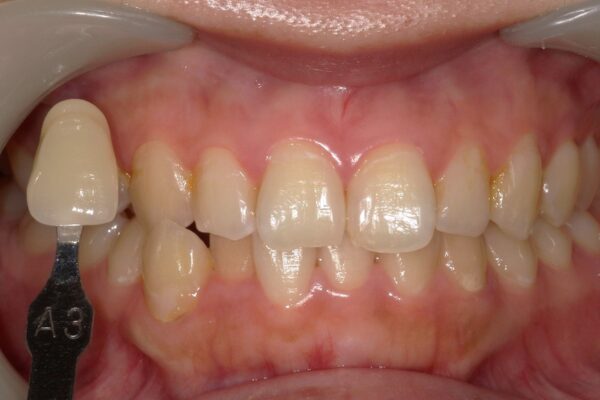

Images